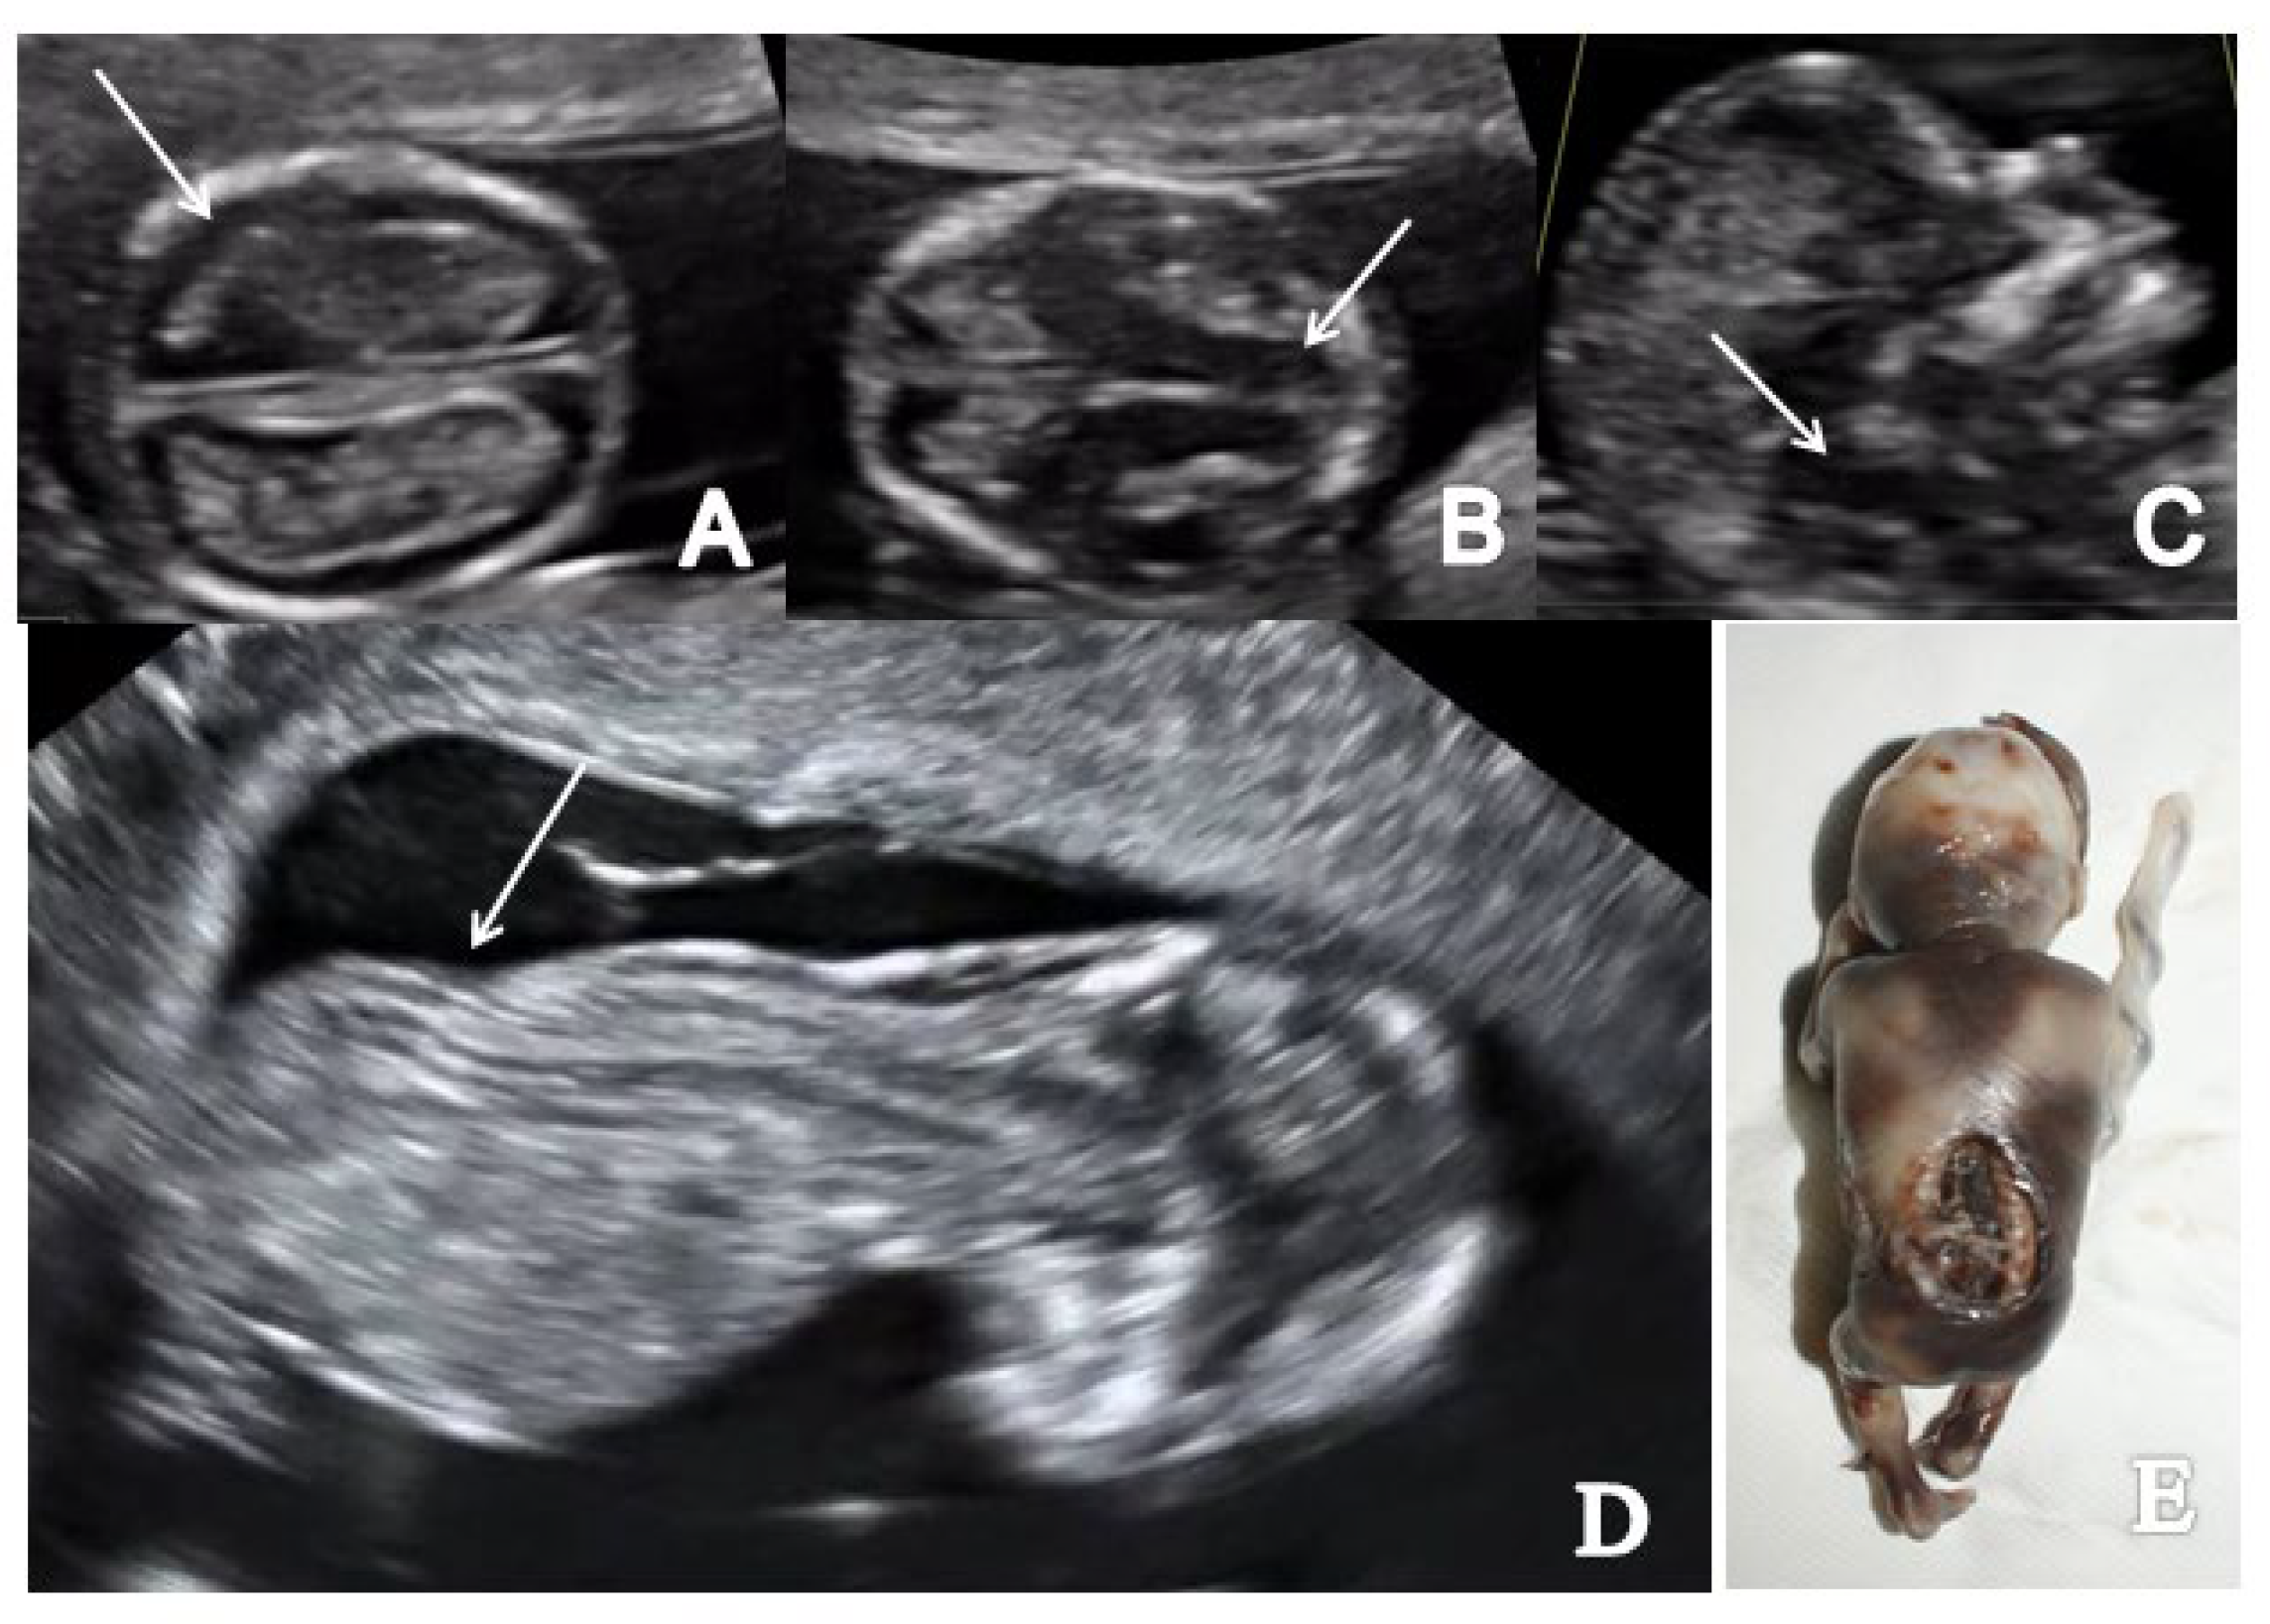

In the axial plane, we noted a decreased intracranial fluid with enlarged choroid plexus in one of three OSB cases while the ‘crash’ sign was obvious in two/three cases. Similarly, in two/three cases of OSB, we noted an abnormal posterior brain (IT, CM and BS/BSOB ratio) (Figure 3 and Figure 4). The single case of meningocele with CSB presented a normal posterior brain anatomy in axial and sagittal view [18]. We found abnormal features of the spine and the overlying skin (kyphoscoliosis, spinal defect or meningocele) in all cases of SB (4/4 cases).

Figure 3.

A case of OSB diagnosed at 12 weeks + 3 days (Case 1): (A) transverse view of enlarged choroid plexus (the ‘dried up’ brain sign, arrow); (B) displacement of mesencephalon and aqueduct of Sylvius and deformation against occipital bone (‘the crash sign’, arrow); (C) mid-sagittal view of the fetal face showing the displacement of BS, which appears thicker (arrow) and with an increased BS/BSOB ratio; (D) sagittal view by transvaginal approach demonstrating the abnormal aspect of the spine—kyphoscoliosis (arrow); (E) specimen presentation of OSB after medical TOP.